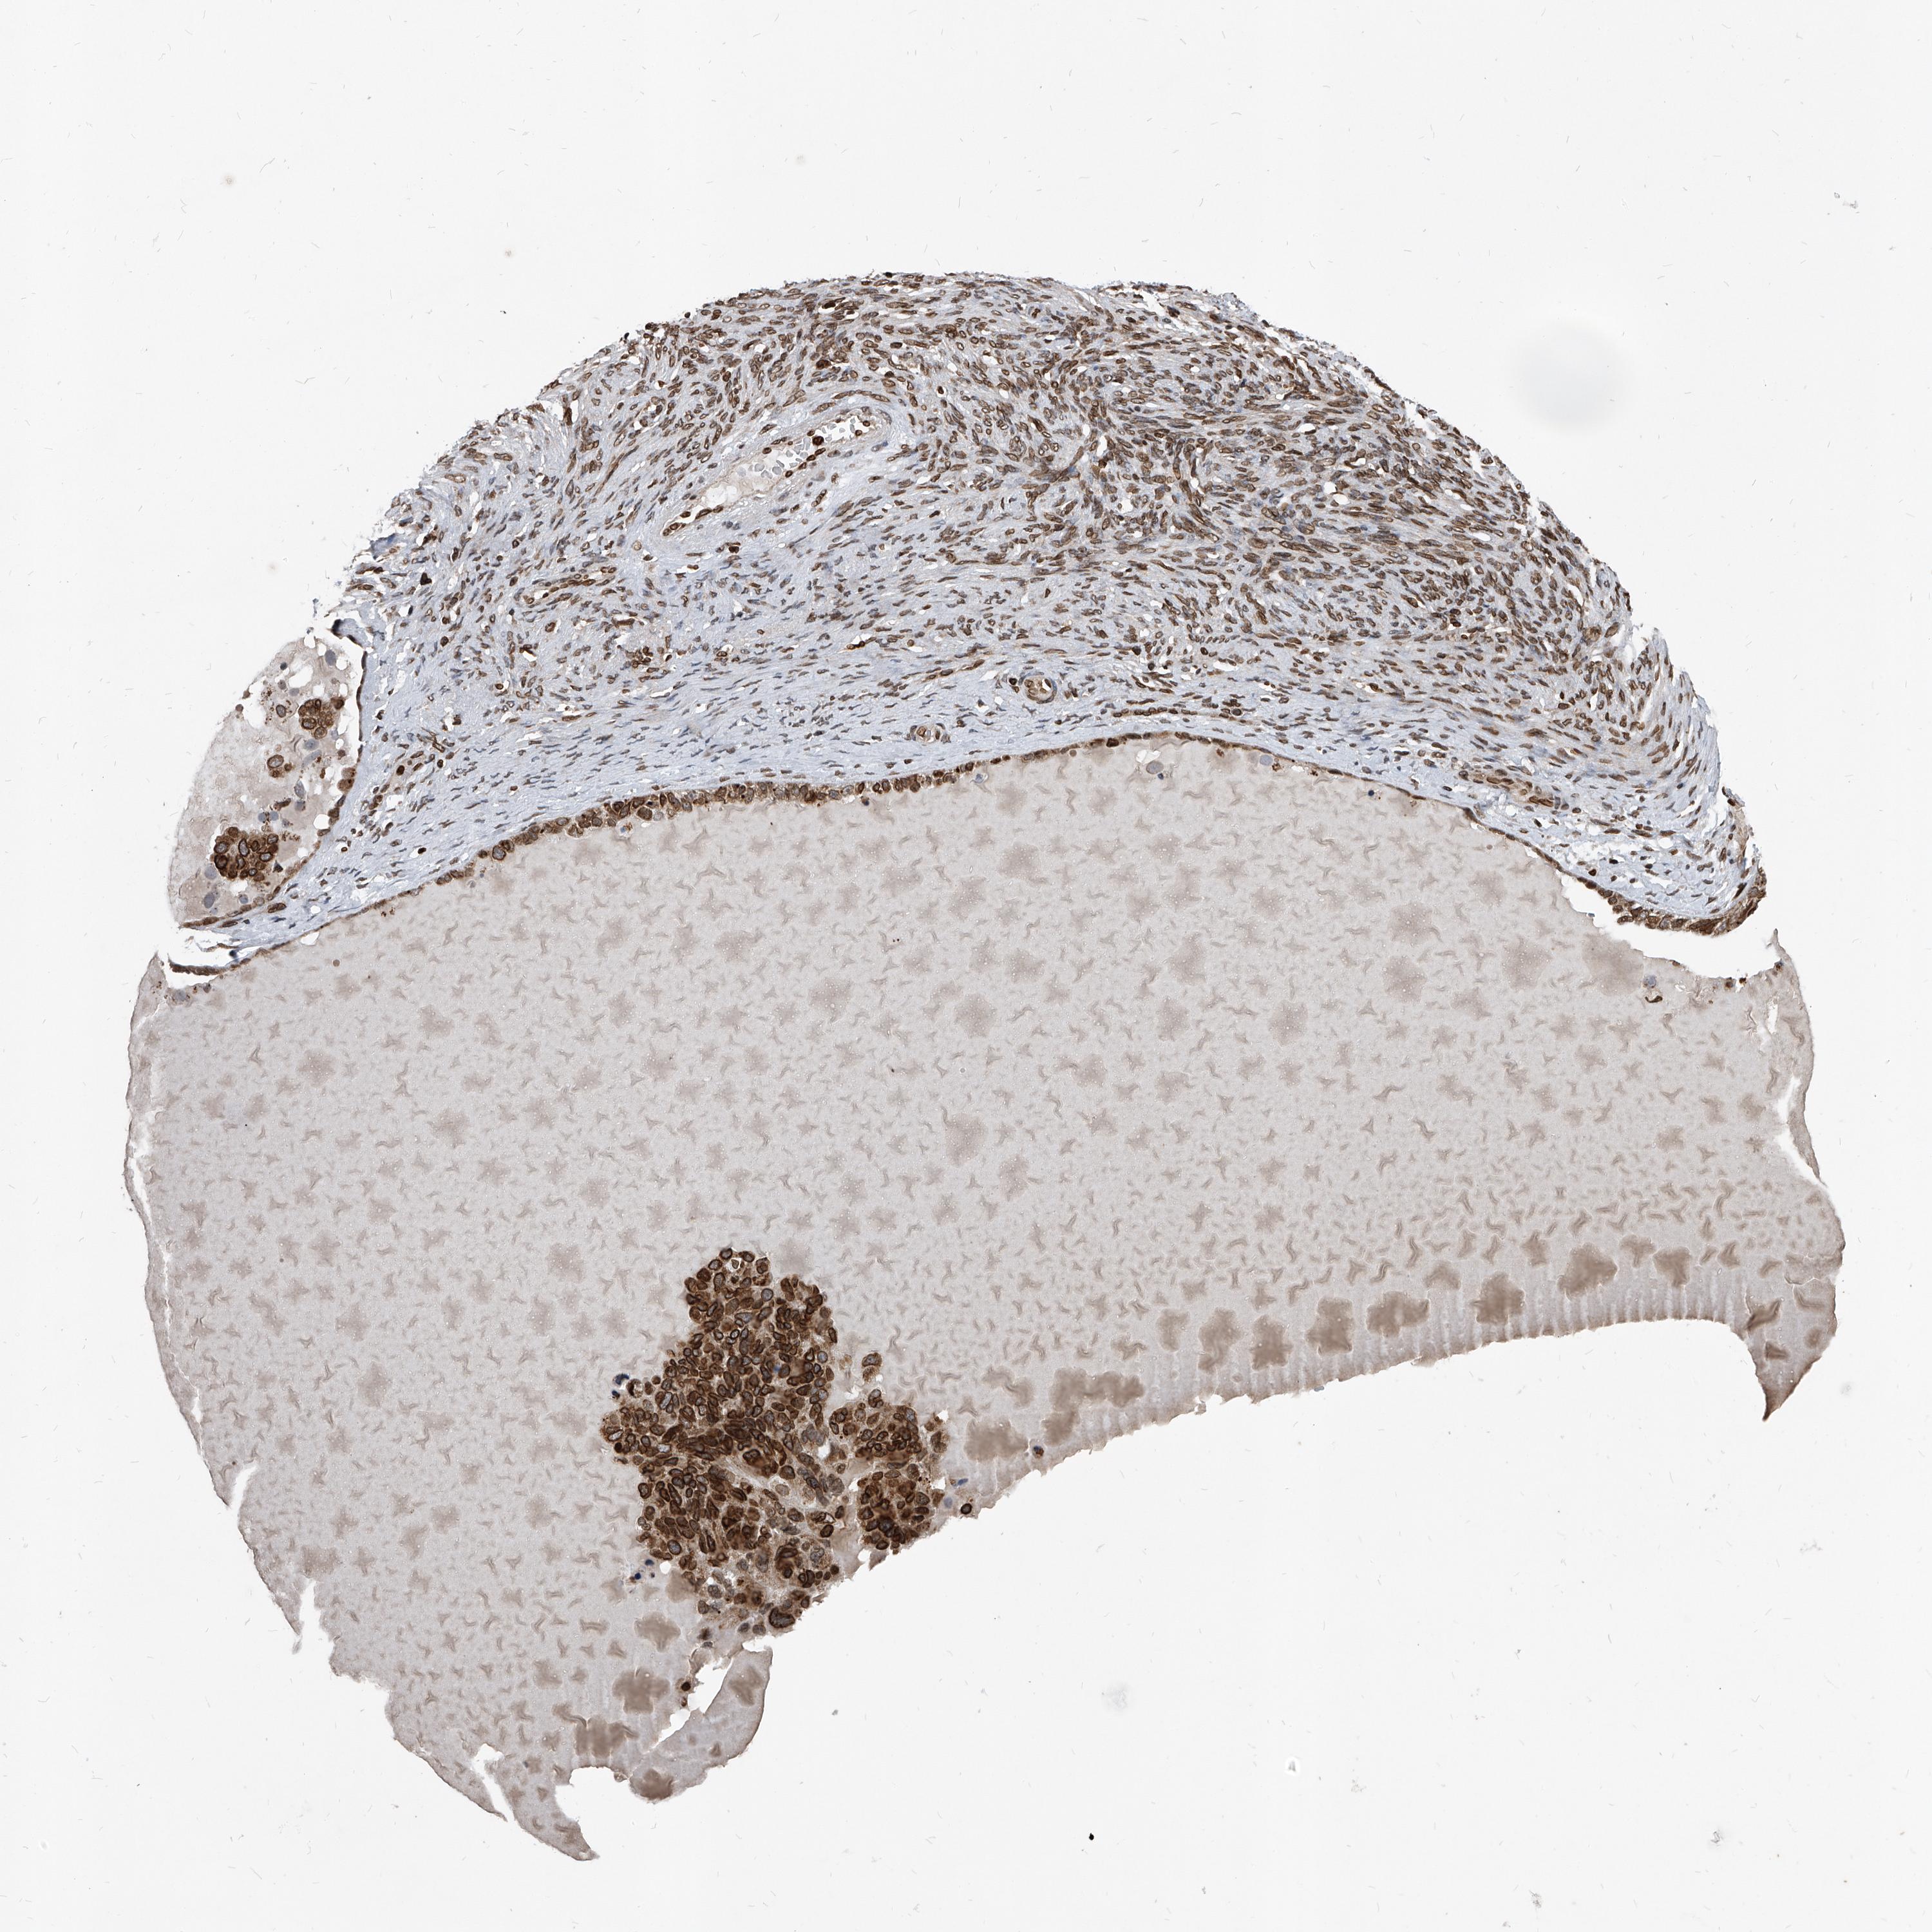

PHF20